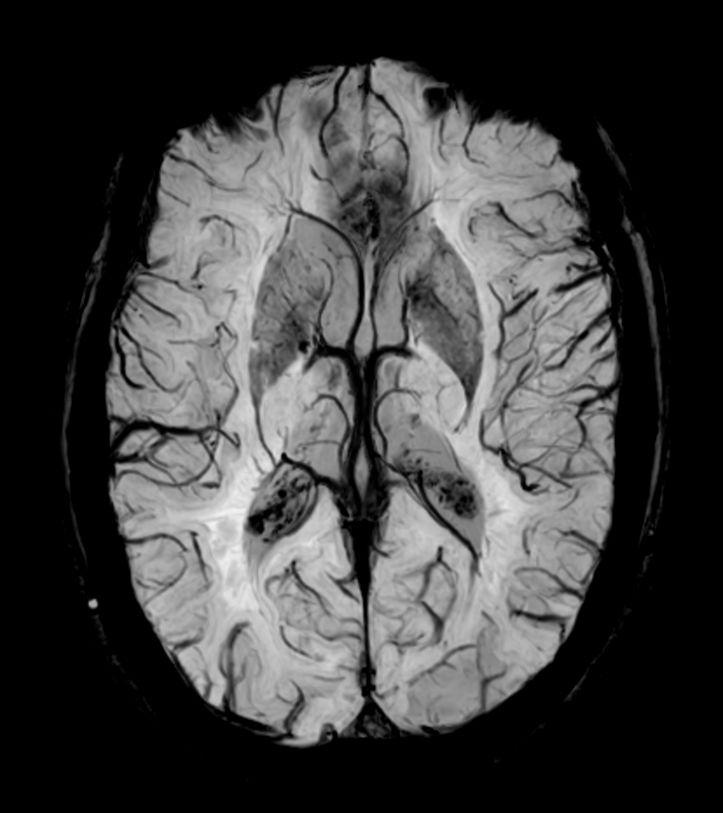

SWIp 6 echoes (Modulus)

SWIp 6 echoes (minIP)

SWIp 6 echoes (Phase)